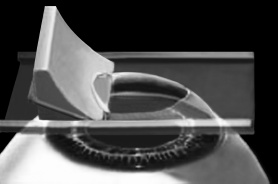

Эпителий роговицы не трогают, так как он – залог быстрого заживления. Накладывают на глаз вакуумное кольцо – стальную присоску кольцевидной формы с присоединенной к нему трубочкой. Через трубочку из присоски отсасывается воздух, чтобы создать относительный вакуум. Отсасывает воздух главный аппарат для проведения ЛАСИКа – микрокератом. Это прибор размером с коробку из-под обуви. Его предназначение – срезание поверхностной крышки роговицы. К глазу присоединяют вакуумное кольцо, окружающее роговицу. Глаз четко фиксируется относительно кольца и сдвинуться с места может только с кольцом, в отверстие которого выступает купол роговицы. Затем к кольцу присоединяется головка микрокератома. Это второй инструмент микрокератома и соединяется с ним или шнуром, или тонким шлангом. Головка крепится на турбине, и вместе они имеют вид толстой шариковой ручки с обрубленным концом. Эту «ручку» хирург держит в правой руке, а вакуумное кольцо – в левой. Эта «ручка» нужна, чтобы сформировать крышечку роговицы. Внутри головки есть очень острое одноразовое лезвие. Турбина, соединенная с головкой, может двигать одноразовое лезвие туда-сюда, пилящими движениями. Можно резать роговицу, как хлеб, – пилящими движениями. И тут самое главное – скорость. Одноразовое лезвие делает 15000 пилящих движений в минуту. При такой скорости назвать это срезанием роговицы уже трудно, скорее это отслаивание верхних слоев.

Рис. 3. Схема формирования роговичного лоскута с помощью микрокератома.

Иллюстрация с сайта Международного лазерного центра www.optics.ru

Итак, головка присоединяется к вакуумному кольцу и по специальным полозьям двигается над куполом роговицы (рис. 3). Срез, или отслаивание (называйте, как хотите), проводится не полностью, у крышечки (роговичного лоскута) остается маленький участок на периферии, соединяющий ее с роговицей (рис. 4).